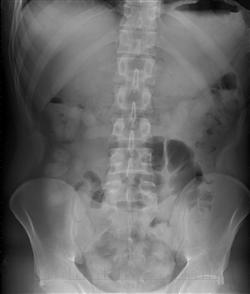

Celníci muže zadrželi a převezli na odborné lékařské vyšetření. Rentgenové snímky prokázaly, že se v jeho břišní dutině nacházejí desítky kapslí o velikosti 3-4 cm s neznámým obsahem.